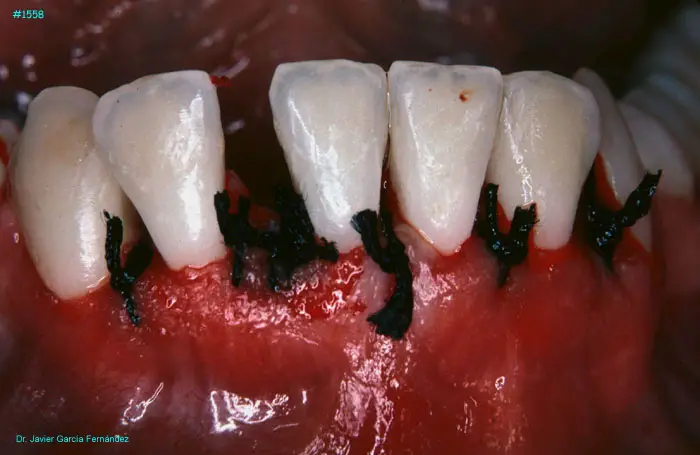

Atlas of Surgical Techniques in Periodontics. Chapter IV. Atlas de Técnicas Quirúrgica en Periodoncia

image 084